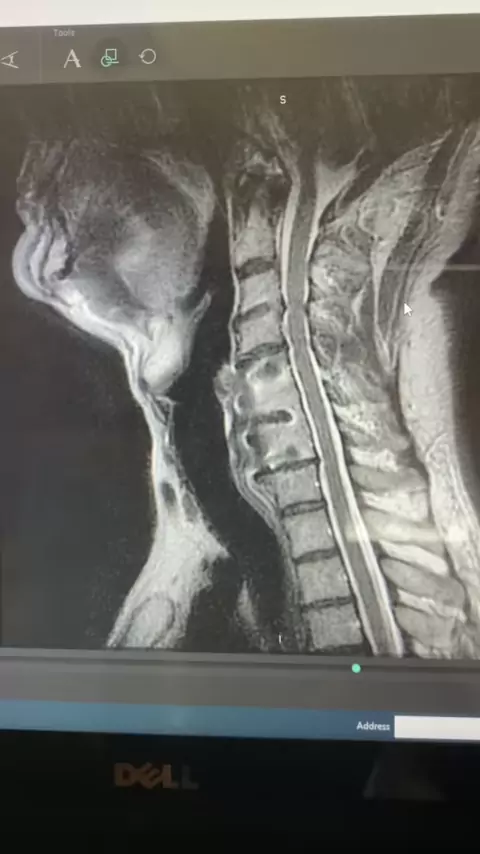

Na ressonância magnética, como é uma hérnia de disco no pescoço? Descubra aqui!! # HerniatedDisk # CervicalSpine # SpineHealth # MRIScan # Backpain # NeckPain # SpinalCare # medicalimaging # HealthEducation # Radiology # SpinalInjury # Anatomy # MedicalKnowledge # Healthcare # Wellness # PhysicalTherapy # SpineAnatomy # Neuroscience # Chiropractic # PainRelief # SpinalHealth # DiskHerniation # MRI # MedicalInsight # HealthAwareness # NeckInjury # SpineCare # Ortho # NeuroHealth # PatientEducati...